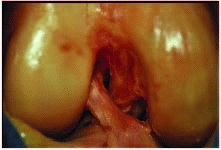

series of 80 skeletally immature patients who underwent surgical

fixation of tibial eminence fractures, Kocher et al.177 found no associated chondral injuries and associated meniscal tear in only 3.8% (3/80) of patients (Fig. 24-1). Associated collateral ligament injury

or proximal ACL avulsion are uncommon, but have been reported.131,252

FIGURE 24-1 Longitudinal meniscus tear associated with tibial eminence fracture.